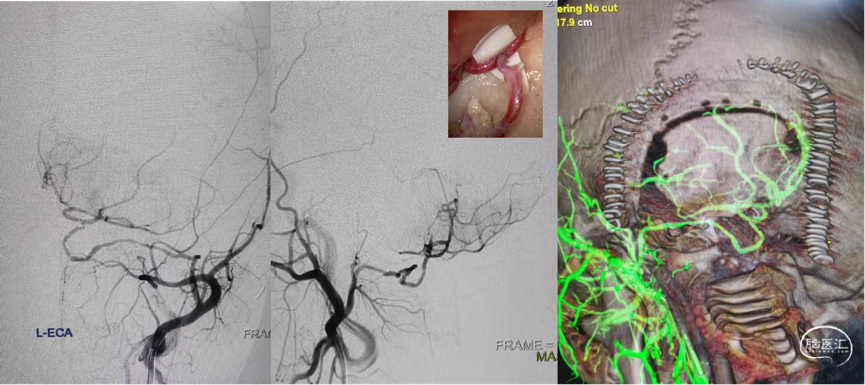

术后造影

血管介入